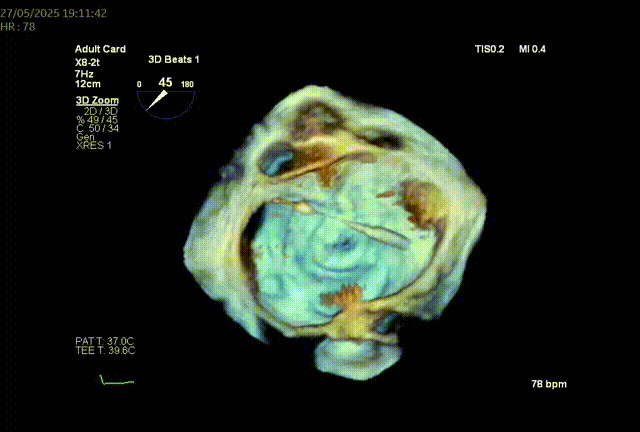

模拟植入26mm的S3瓣膜,评估LVOT阻塞风险:

1.二尖瓣环与主动脉环平面夹角= 128.3°>105°

2.瓣膜与室间隔最短距离= 6.7mm>6mm

3.最小Neo-LVOT面积= 260.4mm2>180mm2

综合评估后LVOT梗阻风险低。